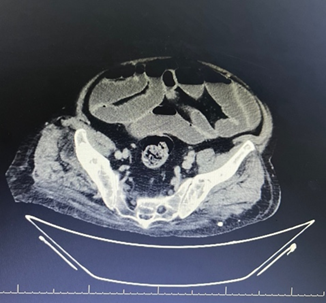

Fig 1: CT abdomen shows dilated small and large bowel loops with proximal ileal wall edema and kinking, likely representing reactive ileus due to bowel wall inflammation, with no evidence of mechanical obstruction

Figure 1